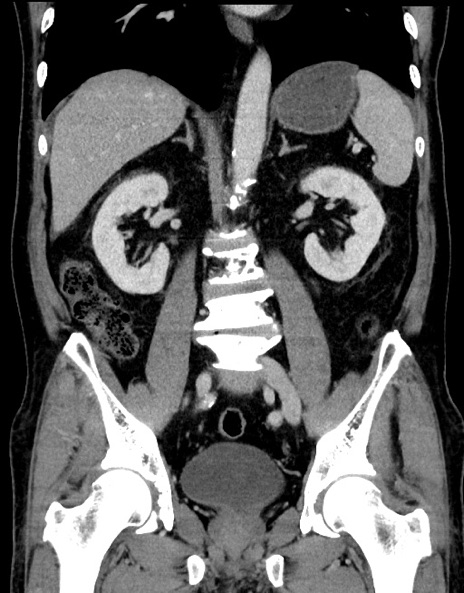

症例15(冠状断像)

【症例】70歳代男性

【主訴】腹痛

【現病歴】今朝から腹痛あり。全体的に痛い。特に左上の方。排ガスが今日はない。冷や汗が出る。

【既往歴】直腸癌術後

【身体所見】左側腹部〜上腹部に圧痛あり。腹膜刺激症状明らかなではない。軽度反跳痛。左下腹部に術後瘢痕あり。

【データ】WBC 7700、CRP 0.02

横断像